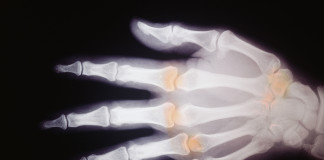

Studio di fase IV

Certolizumab pegol per l’artrite reumatoide

L'efficacia di certolizumab pegol per l'artrite reumatoide è stata valutata in uno studio testa a testa con adalimumab